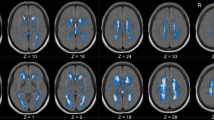

The quality control data of the study population following rs-fMRI preprocessing are reported in Supplementary table 2. The ALFF analysis evidenced the presence of a single cluster of voxels of increased regional neural activity following CEA procedure and no cluster of reduced activity. In particular, the cluster of increased activity consisted of 6260 voxels (cluster mass p-FDR = 0.004704). The majority of voxels identified in the analysis covered the right precentral gyrus (574 voxels, i.e., the 9% of the total amount), the middle frontal gyrus (457 voxels, i.e., the 7% of the total amount), and the anterior division of the cingulate gyrus (299 voxels, i.e., the 5% of the total amount). The complete statistics are reported in Table 4 and a visual representation is reported in Figs. 2 and 3.

Results of the ALFF analysis (neurological orientation). The orangish areas represent areas of increased regional activation following carotid endarterectomy. The complete composition of the cluster of increased regional neural activity is reported in Table 4